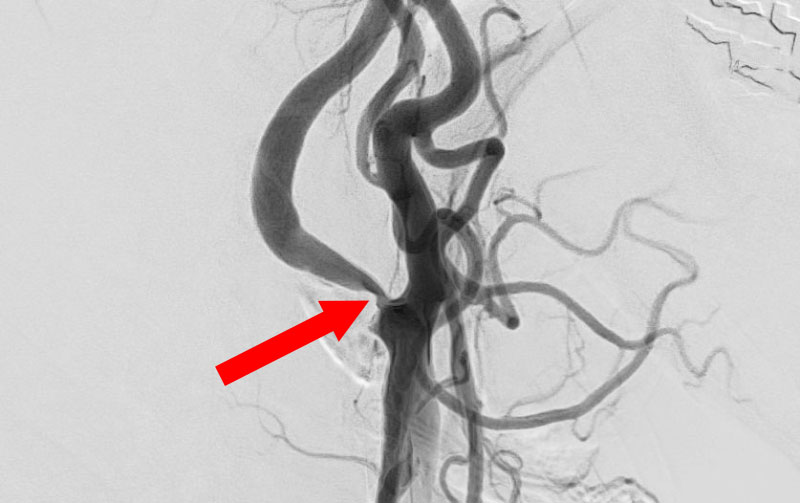

1619

'26年3月11日

左内頚動脈狭窄症

70代

大阪府の病院

手術写真

治療

前

中

後